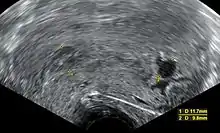

Ultrasound criteria

A review article in The New England Journal of Medicine based on a consensus meeting of the Society of Radiologists in Ultrasound in America (SRU) has suggested that miscarriage should be diagnosed only if any of the following criteria are met upon ultrasonography visualisation:[97]

Miscarriage diagnosed Miscarriage suspected References

Crown-rump length of at least 7 mm and no heartbeat. Crown–rump length of less than 7 mm and no heartbeat. [97][98]

Mean gestational sac diameter of at least 25 mm and no embryo. Mean gestational sac diameter of 16–24 mm and no embryo. [97][98]

Absence of embryo with heartbeat at least 2 weeks after an ultrasound scan that showed a gestational sac without a yolk sac. Absence of embryo with heartbeat 7–13 days after an ultrasound scan that showed a gestational sac without a yolk sac. [97][98]

Absence of embryo with heartbeat at least 11 days after an ultrasound scan that showed a gestational sac with a yolk sac. Absence of embryo with heartbeat 7–10 days after a scan that showed a gestational sac with a yolk sac. [97][98]

Absence of embryo at least 6 weeks after last menstrual period. [97][98]

Amniotic sac seen adjacent to yolk sac, and with no visible embryo. [97][98]

Yolk sac of more than 7 mm. [97][98]

Small gestational sac compared to embryo size (less than 5 mm difference between mean sac diameter and crown-rump length). [97][98]